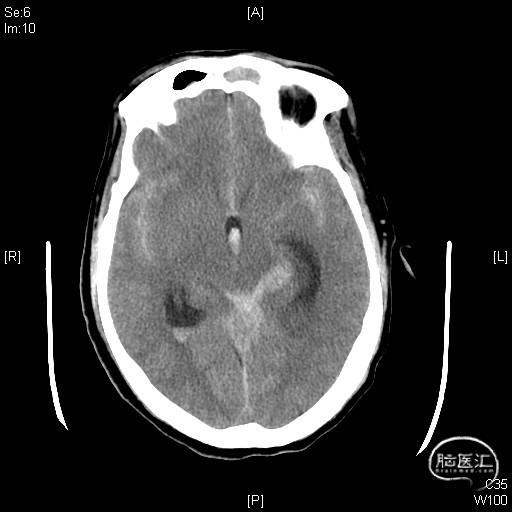

术前头部CTA及胸部CT:左侧PICA动脉瘤破裂出血破入脑室,肺部感染。

术前CT

现病史:患者8小时前被发现意识障碍,邻居急呼120到当地医院,完善CT示:SAH破入脑室,当地医院予气管插管后转入我院,急诊行CTA考虑左侧PICA动脉瘤破裂出血破入脑室,急诊收住院。